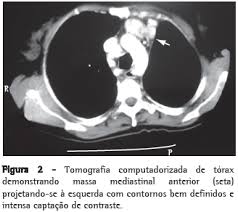

Nódulos hiperplásicos dos linfonodos grandes e benignos. O subtipo vascular de hialina mais comum é caracterizado por pequenos folículos vasculares de hialina e proliferações capilares interfoliculares. As células plasmáticas, em geral, estão presentes e representam outro subtipo dentro das células plasmáticas contendo IgM e imunoglobulina a.